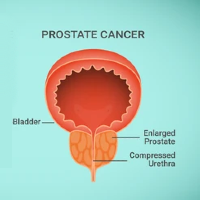

Prostate cancer

Enlarged prostate

Among others, London Bridge Urology specialises in the diagnosis and treatment of prostate cancer, kidney cancer, kidney cancer, kidney stones, TURBT (trans urethral resection of a bladder tumour), prostatitis, enlarged prostate, vasectomy and vasectomy reversal, circumcision, bladder stones and blue light cystoscopy.